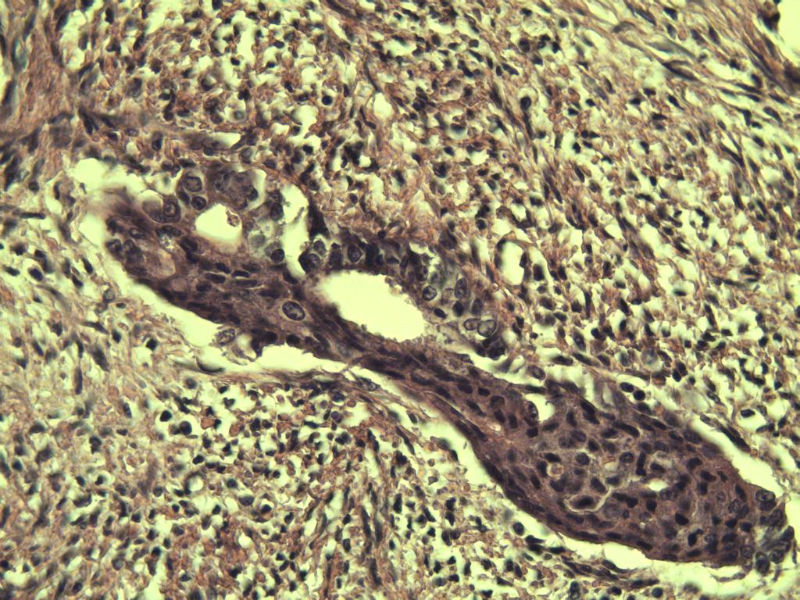

42岁 月经不规则一年 b超发现子宫肌瘤 行全子宫切除术  我取材时发现子宫颈管上段有一质地较硬区 2*1cm  请各位老师看看 是子宫内膜癌不? 谢谢了!

这是子宫颈管上段

子宫颈管上段图1

非癌,考虑子宫内膜异位症或腺肌瘤

肌层内腺体的特点:1、无内膜间质。

2、有鳞化。

3、无异型。所以应该还是个良性病变

非典型性息肉样腺肌瘤。

诊断依据:

1.临床特征:主要发生在绝经前女性,中位年龄39岁,大多数伴有月经紊乱。

2.大体特征:最常见于子宫下段,平均大小为直径2cm,表现为圆形,凸出于表面。息肉样的本质不总是很明显,也有无蒂和广基的肿瘤。

3.镜下特征:上皮成分由杂乱无章排列的不规则的子宫内膜型腺体构成,可以是立方形到矮柱状或假复层。显示有广泛的鳞化区域(本例图11-17均显示鳞化),表现为圆形的“桑葚”(图16-17);间质主要由平滑肌构成,且混有纤维组织。